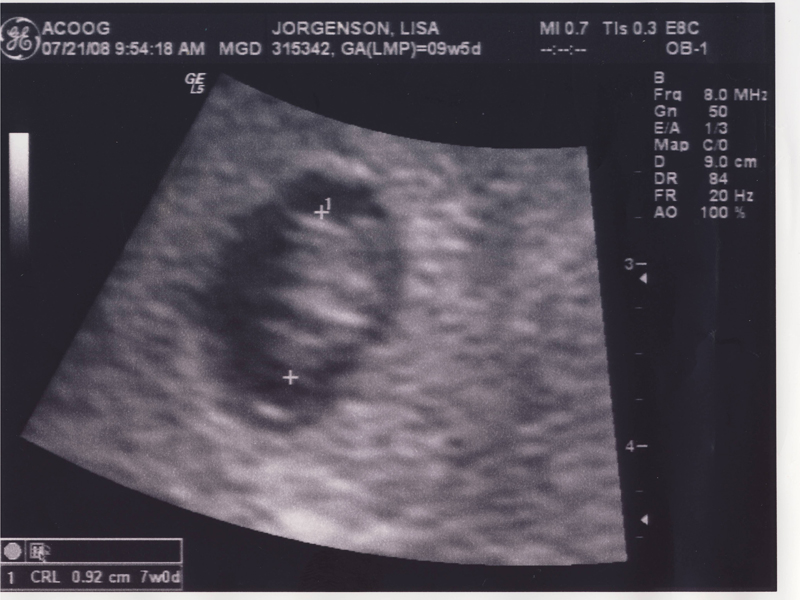

Lisa Jorgenson